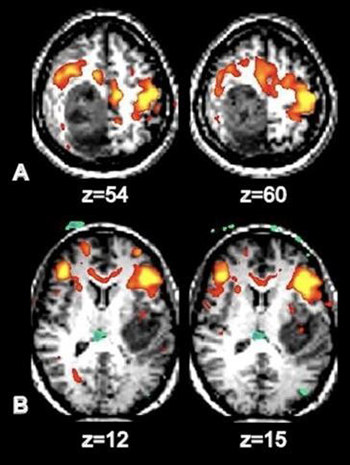

Figura 2:

Identificación de áreas motora y del lenguaje en dos pacientes con glioblastoma:

A) desplazamiento anterior al tumor del área somatosensorial y B) desplazamiento anterior del área de Broca.

AJNR Am J Neuroradiol Oct 2013